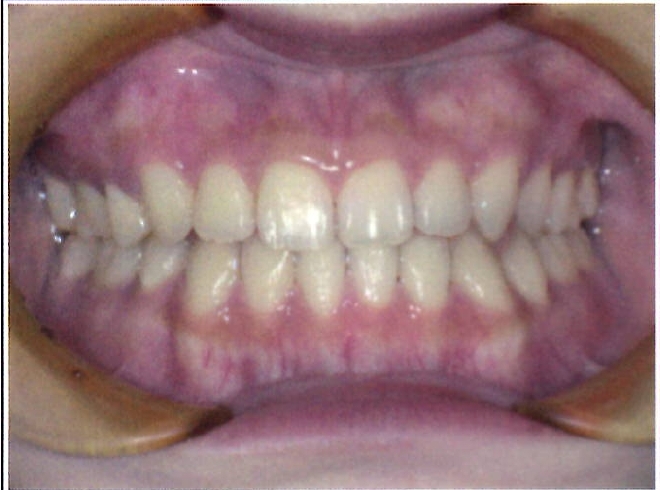

| 主訴・治療前の状態 | 過蓋咬合(噛み合わせが深く、下の前歯が見えない状態)により歯ぎしりができない状態でした。また、上下顎前歯部に叢生(クラウディング・ガタガタ)がありました。 |

| 治療内容 | 矯正治療により、過蓋咬合と上下の叢生を改善しました。 |

| 治療結果 | 適切な被蓋(上下の前歯の重なり)が得られ、下の前歯がきちんと見えるようになりました。上下の前歯の歯並びも美しく整い、しっかりと噛み合うようになりました。機能面・審美面ともに大きく改善した症例です。 |